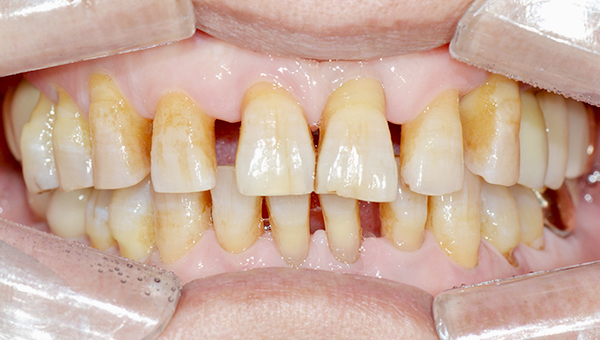

강*란 임플란트 시술 사례

전체 임플란트

2025.02.07

치료 전

2025.08.19

치료 후